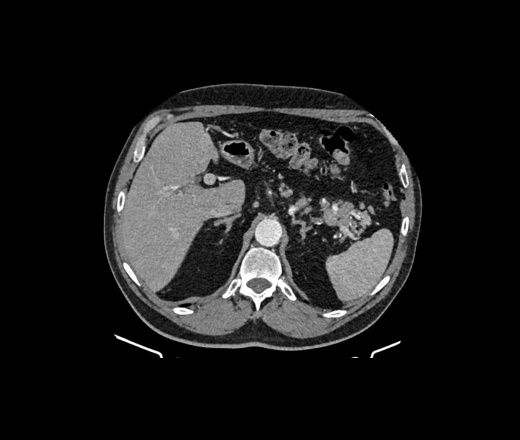

Здравствуйте, подскажите пациент 60 лет, особо жалоб нет, на узи было изменения в печени, в хвосте поджелудочной железы отмечаются немного гиподенсивные изменения может ли это быть раком? на МРТ лучше покажет?

В печени гиперваскулярное образование в 5 сугменте, требует наблюдения. Поджелудочная - ничего плохого не вижу. А вот лимфоаденопатия выражена. Если мтс, то откуда - не знаю